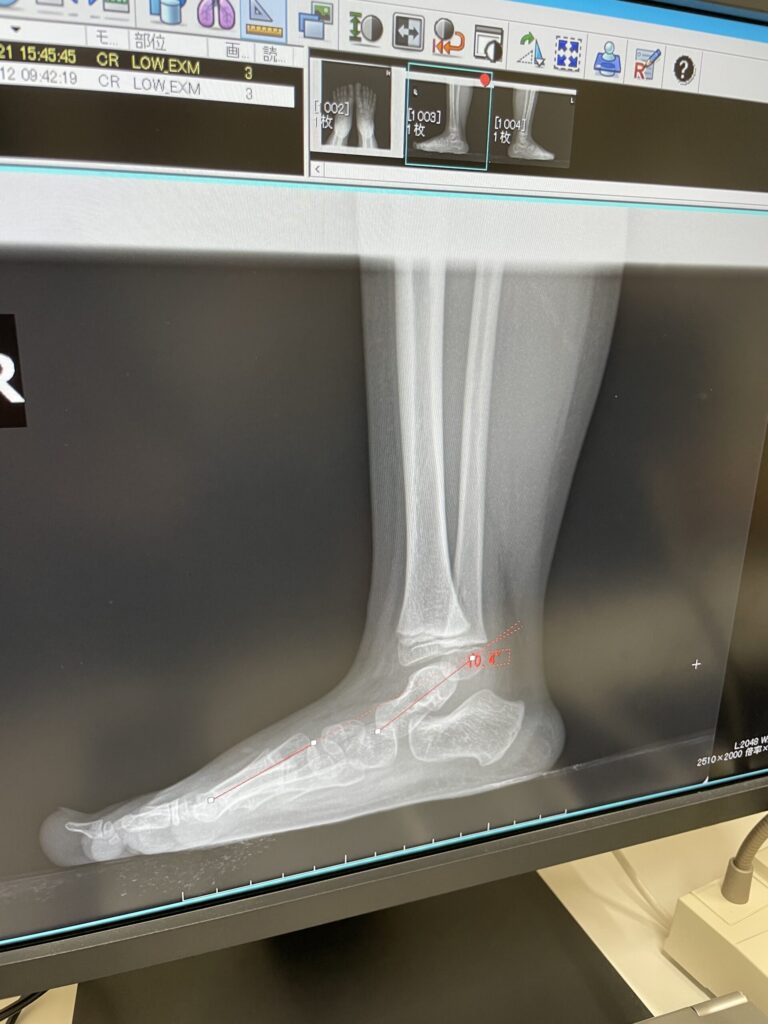

インソールなしの状態

インソールが完成し、整形外科で靴を履いた状態のレントゲンを撮影。

すると――

履いていない状態と、履いた状態では 全然違う

1枚目の写真。インソール無しの状態では骨がぺたんと沈み込んで土踏まずのカーブが一切ありません。

2枚目の写真。扁平足だった部分の骨が、しっかり持ち上がっていました。